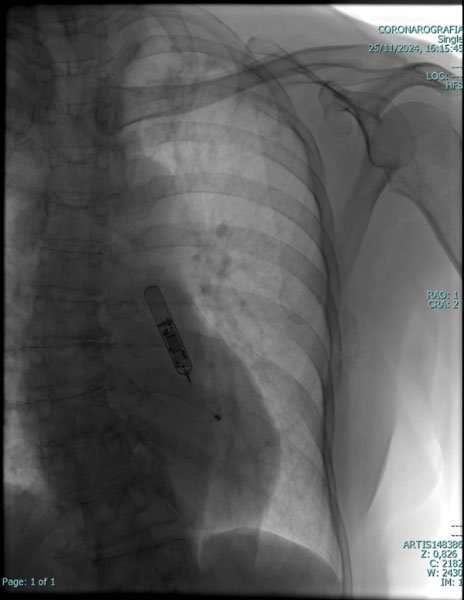

PACE MAKER LEADLESS

L'evoluzione della ricerca e conseguenzialmente della tecnologia in particolare in campo cardiologico, ha consentito di sviluppare sistemi di stimolazione cardiaca miniaturizzati e “senza fili” (“leadless pacemaker”), in cui il generatore d'impulsi e gli elettrodi sono contenuti in una singola unità totalmente intracardiaca, eliminando quindi la presenza degli elettrocateteri convenzionali e della tasca pre-pettorale sottocutanea.

La terapia con pacemaker (PM) senza elettrocateteri (“leadless”) rappresenta una realtà nel campo dell'elettrostimolazione cardiaca. I PM leadless hanno come obiettivo primario quello di ridurre le complicanze legate all'introduzione di elettrocateteri endocavitari e alla creazione della “tasca sottocutanea” in regione sottoclaveare, e si propongono come valida alternativa nei pazienti con controindicazioni alla stimolazione cardiaca tradizionale. I vantaggi dei pacemaker leadless sono legati essenzialmente alle loro piccole dimensioni, al minimo peso, all'assenza di meccanismi di connessione tra generatore ed elettrodi, dato che questi coesistono in una singola unità, alla procedura di impianto mini-invasiva transcatetere, e al considerevole minor rischio di infezioni.

I pacemaker leadless possono essere posizionati nella cavità ventricolare ed eventualmente, atriale destra con una procedura mini invasiva per via transcatetere con approccio transcutaneo utilizzando la vena femorale (dall'inguine), attraverso uno speciale introduttore. Il sistema non richiede quindi la creazione di una tasca e non lascia cicatrici esterne visibili.

Questo nuovo tipo di Pacemaker è totalmente intracardiaco è formato da un dispositivo fissato direttamente all'interno del ventricolo destro, ed eventualmente atrio destro. Nel caso di un impianto bicamerale (atrio e ventricolo destro), grazie ad un innovativo sistema di comunicazione, i device riescono a “parlare“ tra di loro per sincronizzare le due camere cardiache. L'introduzione di questo tipo di tecnologia  leadless da inizio ad una nuova era del pacing intracardiaco.